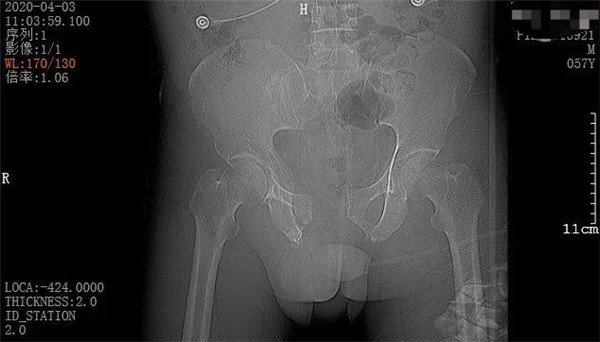

4月3日一早,和往常一樣,家住六橫的趙大叔騎著三輪車去買菜,誰知經(jīng)過下坡路時剎車失靈,趙大叔重重地撞上了一根柱子后,三輪車壓倒了他身上。趙大叔頓時感覺身體疼痛不已,無法轉(zhuǎn)身、站立。在路過市民的幫助下,他迅速被送至當(dāng)?shù)蒯t(yī)院。經(jīng)CT拍攝顯示,趙大叔骨盆骨折、腹腔積血。此時,大叔突然出現(xiàn)了呼吸急促、血壓不穩(wěn)定等情況,聞訊而來的家屬當(dāng)即表示要到廣安醫(yī)院治療,并火速聯(lián)系車子送往我院。

CT檢查報告